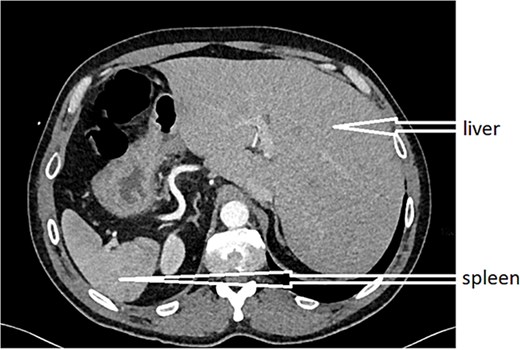

After obtaining informed consent and providing the patient with information about the case, he was transferred to the operating room after preparation, including rehydration, proton pump inhibitor (PPI), antibiotic therapy, and analgesia. Urgent exploratory laparoscopy confirmed the CT findings: retrocecal appendicitis with minimal peritoneal effusion (Fig. 3) in the Douglas pouch. A careful dissection of the appendix from its mesentery was performed, followed by appendectomy (Fig. 4), lavage, and drainage.